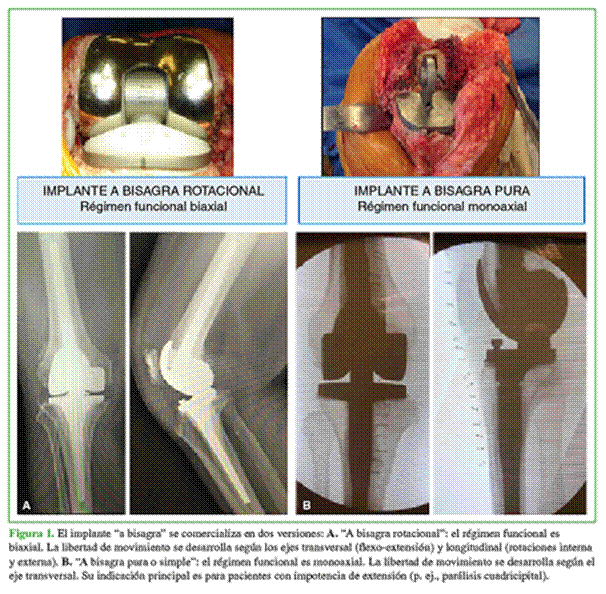

En el trabajo citado, el implante es ya presentado con el símbolo de “marca registrada” (“Endo-Modell®”) (“Scharnierendoprothese Endo-Modell®. Modell mit Zukunft”)5 (Figuras 1 y 2).

En 2000, se comunicaron la experiencia y los resultados luego de 20 años de aplicación del implante. El título de la publicación referida incluye una frase hoy emblemática, desde la perspectiva de los actualmente ya 40 años de prestación brindada por el implante: “Prótesis a bisagra Endo-Modell®. ¿Un modelo con futuro?”.